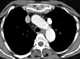

Left superior vena cava

The superior vena cava (SVC) is the superior of the two venae cavae, the great venous trunks that return deoxygenated blood from the systemic circulation to the right atrium of the heart. It is a large-diameter (24 mm) short length vein that receives venous return from the upper half of the body, above the diaphragm. [Source: Wikipedia ]